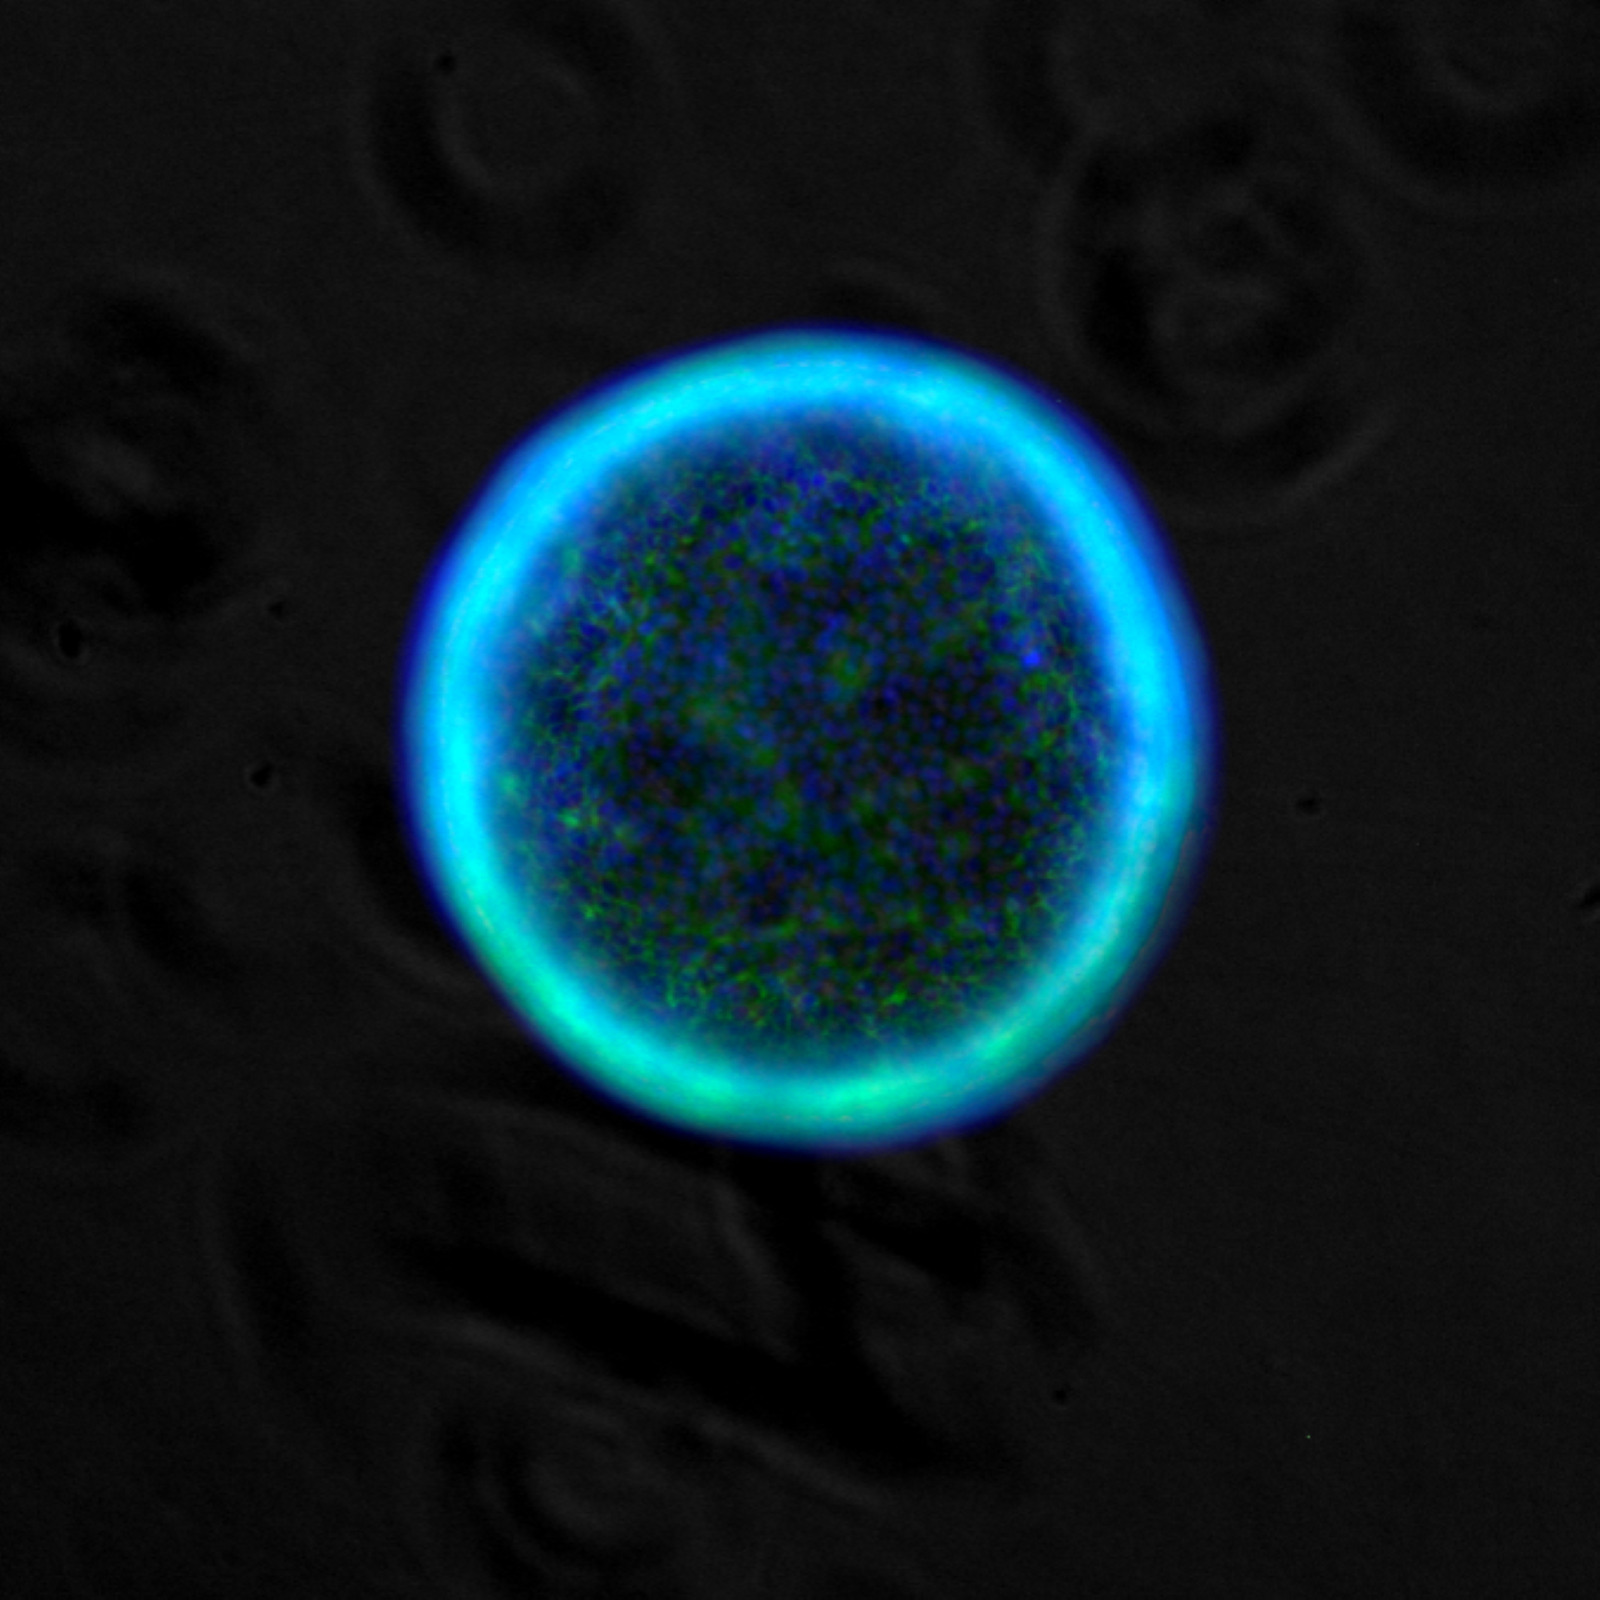

A TU PER TU CON LE CELLULE BUONE E “CATTIVE”

Attraverso giochi e laboratori aperti per tutte le età, descriveremo le differenze tra cellule normali e tumorali, illustrando in modo divulgativo e interattivo le loro caratteristiche, i processi alla base della trasformazione di una cellula verso la tipologia tumorale (autofagia, alterazioni del microbiota e del sistema immunitario) e gli stili di vita che possono influenzare il corretto mantenimento della funzionalità cellulare. Il percorso si svilupperà attraverso la creazione di semplici modelli sperimentali per studiare i tumori in provetta, osservazioni al microscopio di cellule sane e tumorali, realizzazione di modelli divulgativi della cellula e di corretti stili di vita per preservare i processi alla base della normale funzionalità cellulare, piccoli esperimenti, questionari sulle abitudini alimentari, descrizione delle strategie anti-cancro utilizzate nella ricerca farmacologica e degli effetti della presenza del cancro.